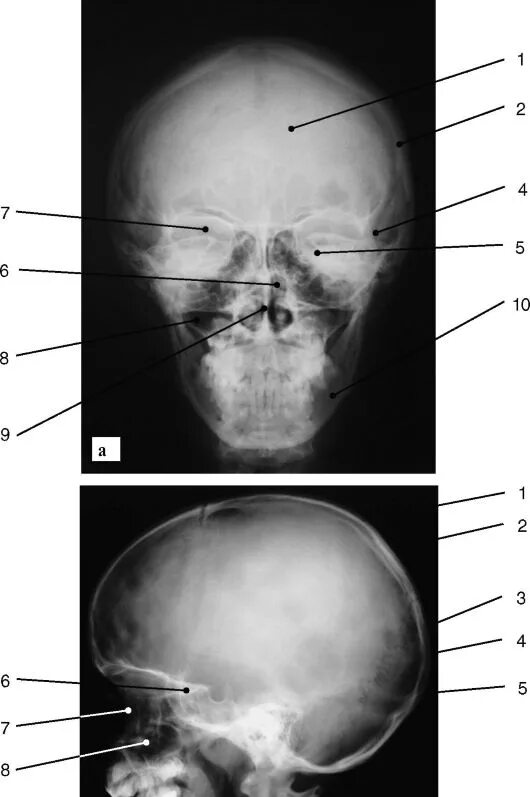

Проекции рентгенограмм черепа